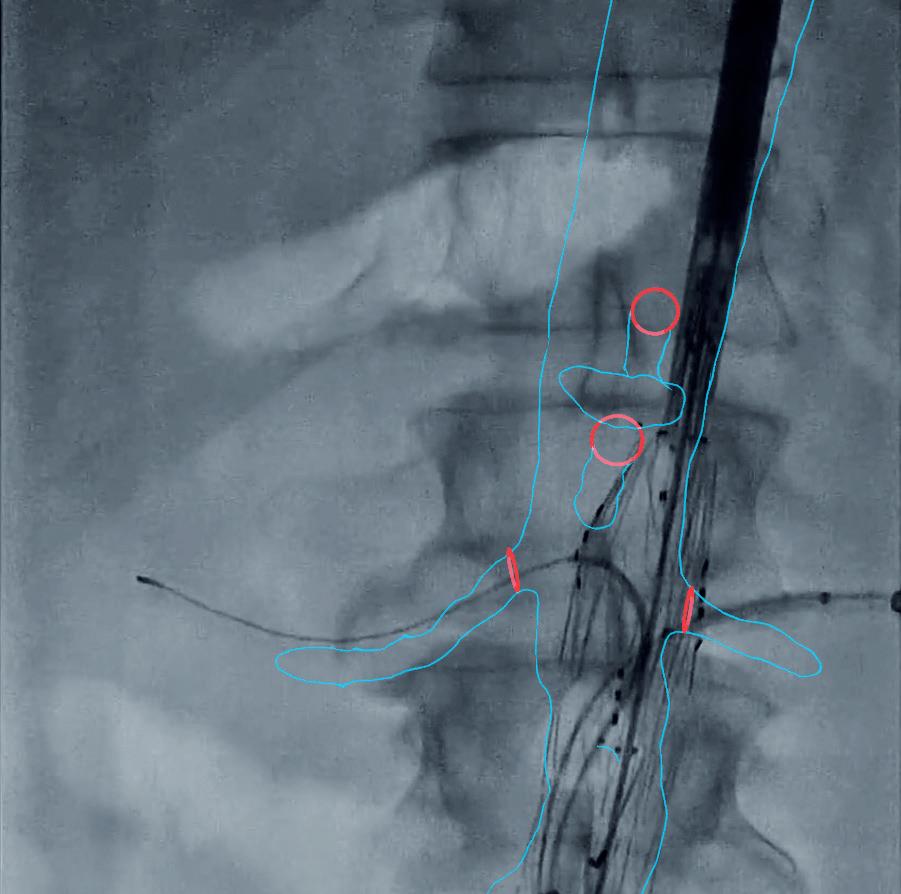

“The field of vascular surgery and the endovascular repair of abdominal aortic aneurysms has been quickly evolving.

As we’ve been able to fix more complex aneurysms, we’ve needed intraoperative assistance for the proper placement of stent grafts,” Ross continued.

One example includes a Cydar Medical AI solution to model how vessels move and are deflected by the introduction of different wires and instruments, she said.

“Preliminarily, use of this technology has been found to decrease important metrics for vascular surgeons, such as radiation exposure, fluoroscopy time and procedure times.”